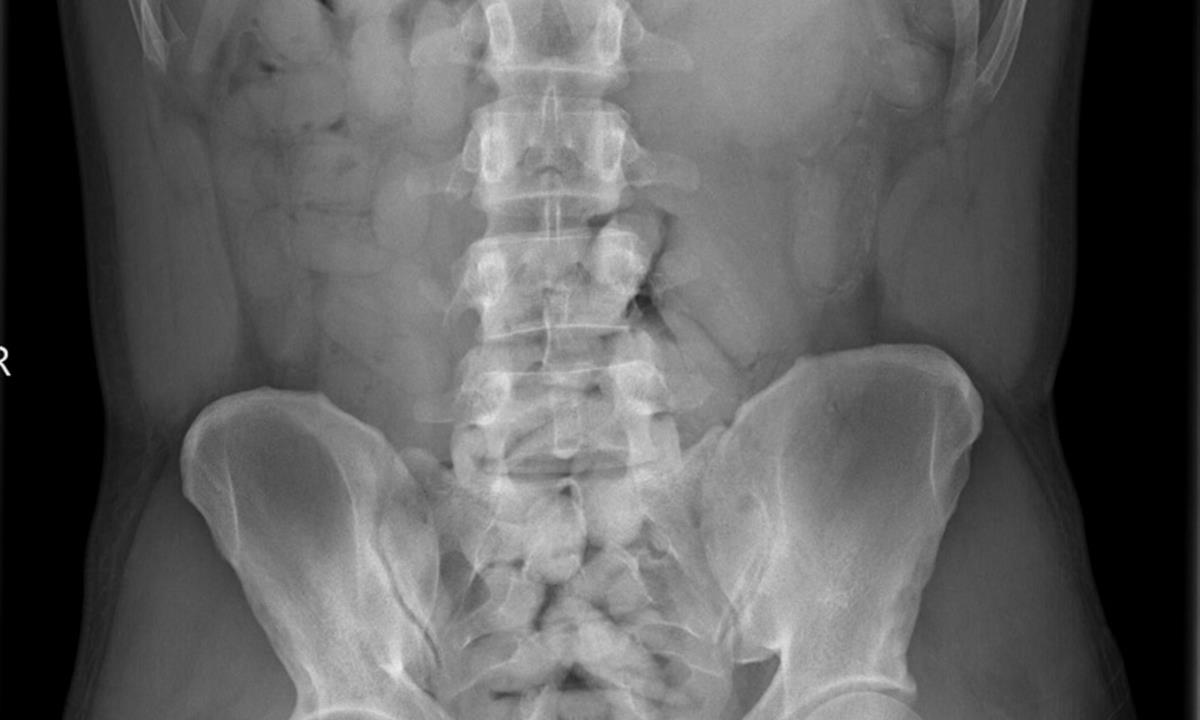

Celníci proto u Nigerijského cestujícího, který byl při kontrole značně nervózní, provedli narkotest, který reagoval pozitivně. Následné RTG vyšetření potvrdilo v obsahu pasažérova žaludku přítomnost několika desítek spolykaných speciálních kapslí. Těch za 24 hodin polykač na speciálním zdravotnickém zařízení vyloučil neuvěřitelné množství 80 kusů o celkové váze 900 gramů. Všechny kapsle obsahovaly kokain vysoké kvality, jehož hodnota by na černém trhu dosáhla sedmi milionů korun. Případ byl předán do vyšetřování.